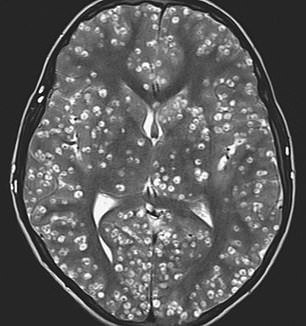

An MRI brain scan showed he had cysts throughout his brain, with the damage being consistent with neurocysticercosis.

An MRI scan revealed the teen had numerous cysts in the outermost layer of his brain (cerebral cortex), which is responsible for thinking and processing information.

There were lesions in his brain stem, which is located at the base, and sends signals between the brain and the rest of the body.

Cysts were spotted in his cerebellum, located at the back of the brain responsible for coordinating voluntary movements like speech, coordination and posture.

Doctors said the extend of the damage was consisted with that of neurocysticercosis, which occurs when the parasitic larvae Taenia solium invades the body from the intestine, and builds up in the nervous system, eyes, skin and muscles.